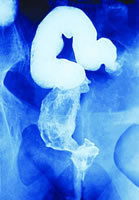

英国牛津大学Goldacre等学者将溃疡性结肠炎、克罗恩病以及乳糜泻患者的肿瘤发生情况与对照人群进行比较发现,这3种肠道疾病患者的肿瘤发生危险增高,尤其是溃疡性结肠炎、克罗恩病患者的结肠癌发生率显著增高[Eur J Gastroenterol Hepatol 2008,20(4)∶297]。

研究从英国中南部地区的国家卫生服务体系(NHS)医院中纳入溃疡性结肠炎患者6990例、克罗恩病5127例、乳糜泻1997例和对照组457071例,平均随访时间分别为8.5年、10年、11.2年和11.6年。

结果显示,将随访第1年的肿瘤发生病例除外,与对照组肿瘤发生情况相比,溃疡性结肠炎患者发生肿瘤的率比(rate ratio)为1.25[95%可信区间(CI)为1.13~1.39],克罗恩病患者的为1.27(95% CI为1.11~1.45),乳糜泻患者为1.16(95% CI为0.94~1.43)。在溃疡性结肠炎或克罗恩病患者中,结肠癌发生危险显著增加[率比分别为2.22(95% CI为1.71~2.83)和1.64(95%CI为1.09~2.39)],且溃疡性结肠炎患者发生直肠肿瘤的危险亦增加[率比为1.84(95% CI为1.27~2.58)]。

在未行结肠部分切除或全结肠切除的溃疡性结肠炎或克罗恩病患者中,发生结肠癌危险的率比分别为5.52(95% CI为 4.39~6.71)和4.81(95% CI为3.52~6.47)。在溃疡性结肠炎患者中,发生直肠癌、肝癌、卵巢癌的危险也有所增加,但肺癌发生危险有所下降[率比为0.72 (95% CI为0.50~0.98)]。

此外,研究还提示,克罗恩病患者宫颈癌发生危险的率比升高[2.63 (95% CI为1.12~5.29)],乳糜泻患者发生非霍奇金淋巴瘤的危险增加[率比为3.28 (95% CI为1.49~6.28)]。

研究者认为,溃疡性结肠炎、克罗恩病和乳糜泻3种胃肠道疾病患者发生肿瘤的危险性均高于其他疾病,并且每种疾病患者发生癌症的种类有所不同。